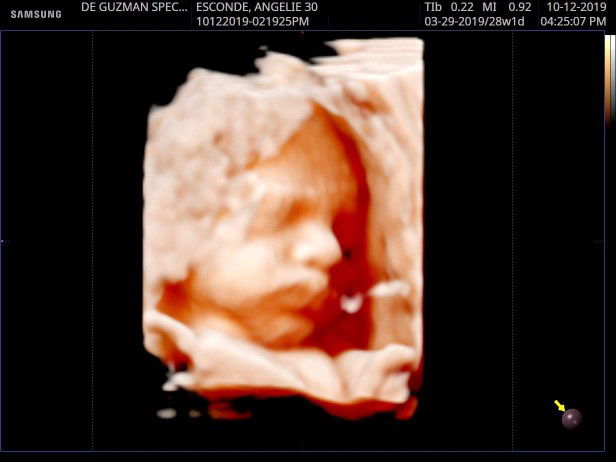

my 28weeks baby girl ??